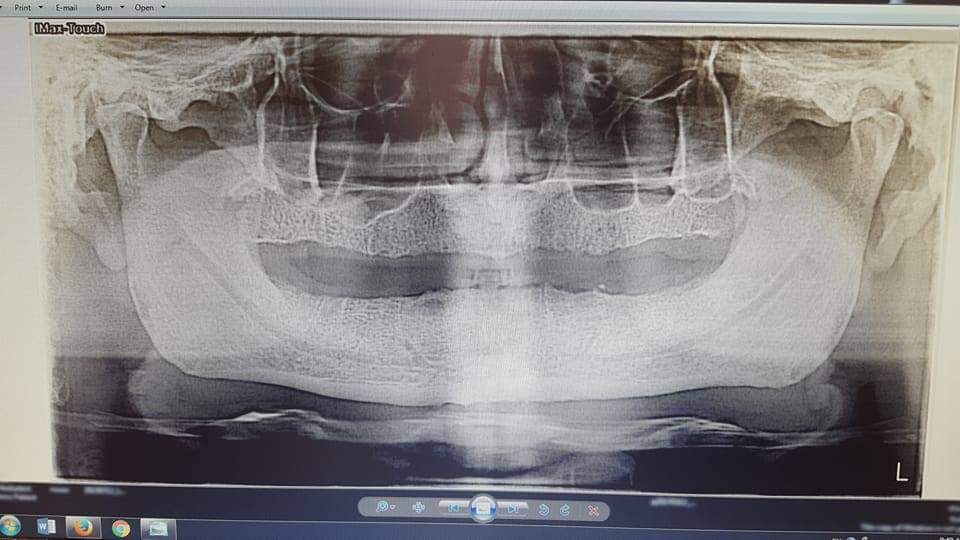

1.وتكمن الحالة الأولى لرجل يبلغ الثامنة والثلاثين 38 من عمره فقد جميع أسنانه(0 سنّ) نتيجة ضعف جيني وإهمال وظروف اخرى…